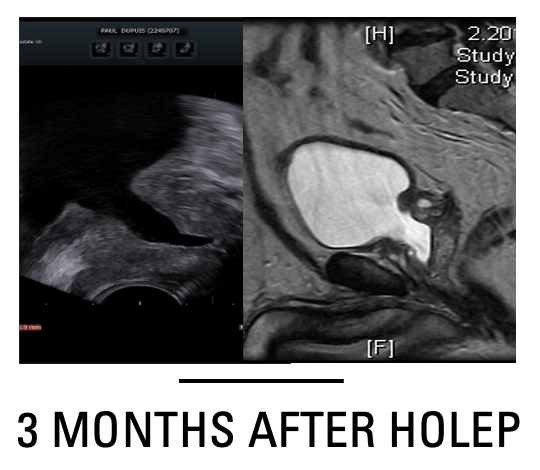

Veil sparing Holmium Laser Enculeation of the Prostate (Lobe by Lobe HoLEP)

Veil sparing HOLEP was performed in step manner approach abbreviated for sake of learning as (IT PAS ABCD). I, incision of the prostate from the deepest groove at the bladder neck till just lateral to the Veru Montanum. T, trough creation, it means widening the incision by incising underneath the 2 lateral lobes with slight pressure applied by the scope to have a wide channel allowing free flow of irrigant while doing apical dissection. This trough is similarly created if we have 2 deep grooves with prominent median lobe by enucleating median lobe first. P, plane development, this step is done by extending mucosal only incision laterally over the apical lateral bulge followed by blunt enucleation of the lateral lobe. A, apico-lateral dissection, it entails upward enucleation of the prostate apex till 3 O’clock position on the left and 9 O’clock position on the right. S, sphincter liberation or strip cutting, where the scope is rotated 180 degrees up with fiber facing 12 O’clock position and mucosal attachment of the adenoma is cut 1cm proximal to the veru (the adenoma should be stretched slightly towards the bladder neck) from 12 to 3 O’clock position on the left and from 12 to 9 O’clock position on the left. A, anterior dissection, where the adenoma is sharply dissected by cutting in arc-shape from the anterior commissure towards the previously developed apico-lateral plain. Anterior dissection in the distal one third of the prostate entails sharp cutting leaving a veil of tissue anteriorly where a capsular plain is poorly identifiable. Later a combined sharp and blunt dissection could easily develop a capsular plain that continues laterally. B, bladder neck dissection, once the bladder neck fibers are identified anteriorly, they were cut transversely by laser. C, c-shaped baso-lateral dissection, at this stage the scope is rotated in c-shaped manner from 12 to 4 O’clock positions on the left and from 12 to 8 O’clock positions on the right. In this step sharp laser dissection is used while applying pressure on the adenoma pushing it from lateral to medial. The rotating movements were repeated while withdrawing the scope inside the prostate fossa till joining the previously formed apico-lateral and basal capsular plains. D, detachment and flipping of the adenoma, the adenoma is lifted by the scope toward the bladder neck till we can flip it to the bladder with remaining basal bladder neck attachment cut by laser from lateral to medial till being completely detached to the bladder. #HOLEP #ANATOMICAL ENDOSCOPIC ENUCLEATION OF THE PROSTATE #enucleation #prostate #learning visit our website https://mansoura-endoacademy.com/ Review the original article https://www.minervamedica.it/en/journals/minerva-urology-nephrology/article.php?cod=R19Y2024N02A0210